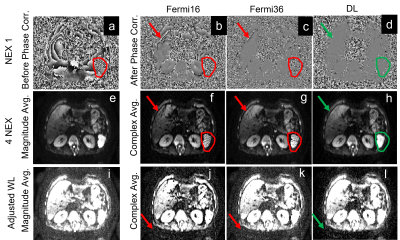

In the liver DWI, both low-frequency phases and high frequency phases (in red contour) were present in single shot DW image, as shown in Figure 4a. Conventional magnitude averaging (Figure 4e) was used to eliminate the impact of these background phases, but suffered from high noise floor, as shown in Figure 4i. Smoothing kernels could be applied to estimate the background phases for complex averaging. However, a large smoothing kernel generated an over-smoothed phase and lost high-frequency spatial information (Figure 4b), resulting in shading artifacts in the averaged image (Figure 4f). In contrast, a small smoothing kernel minimized the smoothing (Figure 4c) and shading artifacts (Figure 4g) but increased signal bias, resulting in a higher noise floor (Figure 4k). Deep learning based phase correction could more accurately correct both high frequency and low frequency phases in tissues (Figure 4d), eliminating shading artifacts (Figure 4h) while minimizing noise floor in the averaged image (Figure 4l).

Figure 4. Liver DWI images (b=1000). (a-d) are the phase maps pre-/post- phase correction; (e-l) are the magnitude and complex averaged images with different window levels. Body DWI often uses magnitude averaging and shows high noise floor (i) and complex averaging is challenging due to large phase variations (a). Compared to a large kernel, small kernel could capture some high-frequency phases and reduce banding artifacts (g vs f), but still fails in some regions and increases the noise floor (k vs j). DL-based phase correction showed lowest noise floor and banding artifacts.